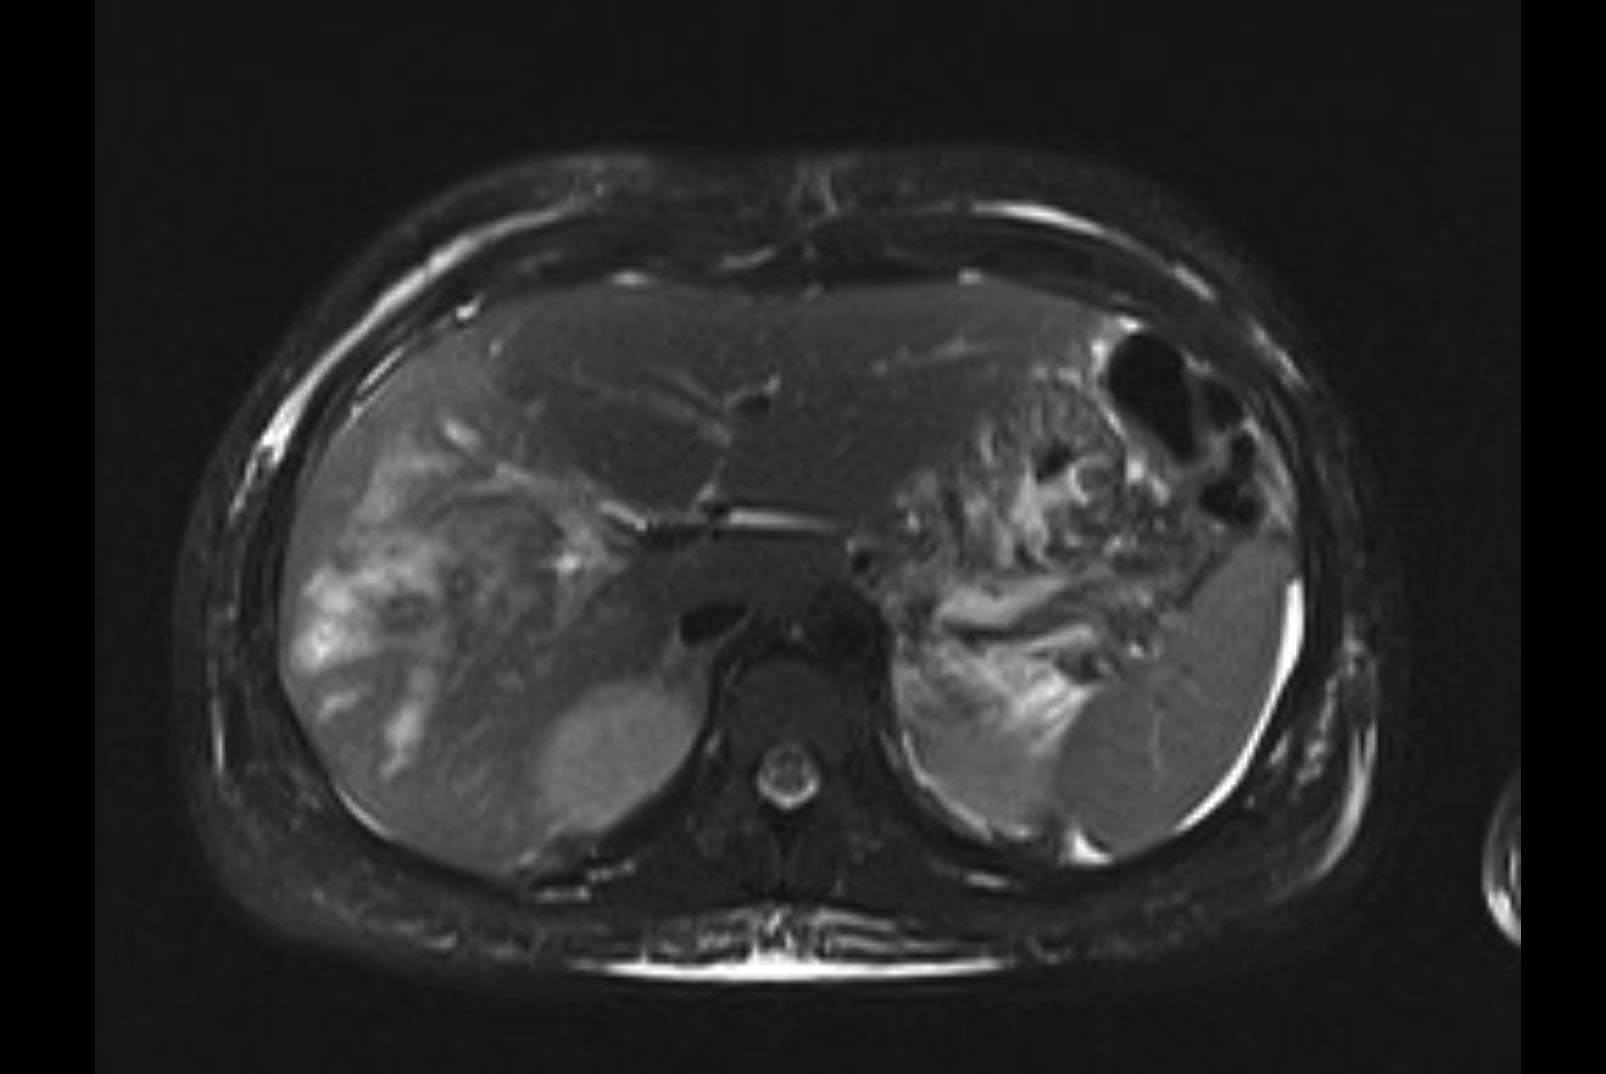

MRI T1

MRI T2

Imaging analysis

Based on initial findings, which issue(s) would you be most concerned about?